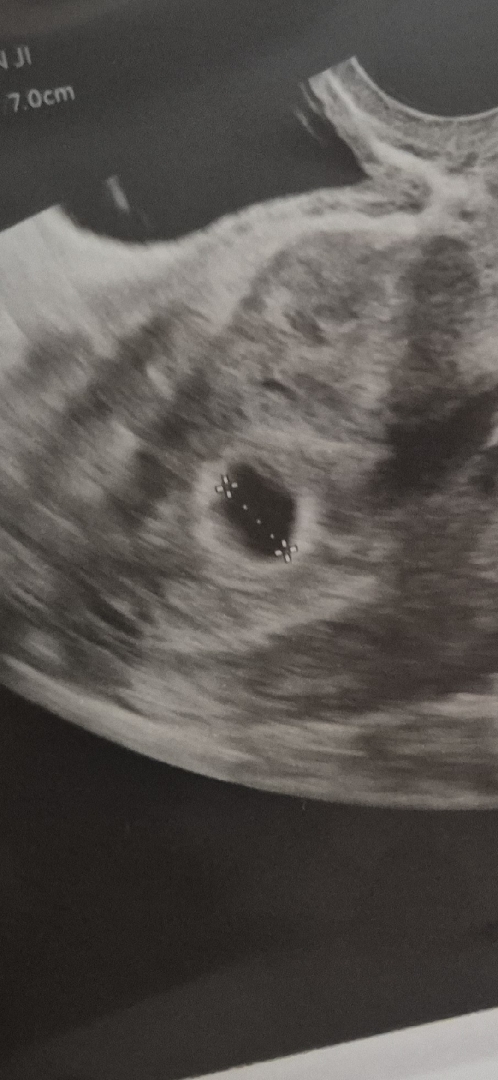

난황이 보이는걸까요

5주 5일차 초음파인데 제가 생리가 불규칙해서 좀더 늦을수도 있다고 하셨거든여 난황이 보이는건지 아닌지 모르겠어서 담주에 다시한번 가보려구요..ㅠㅠ 너무 걱정돼요..